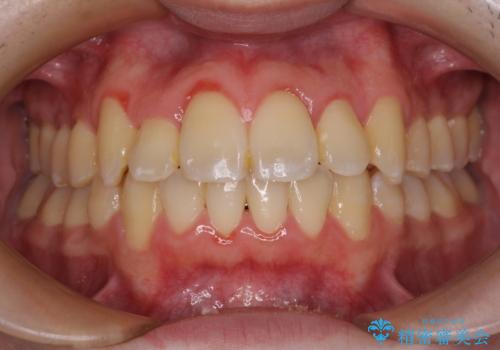

全顎的なクロスバイト 補助装置を用いてワイヤー矯正

- 八重歯や奥歯の噛みにくさを気にして来院された患者様です。

前歯のクロスバイトや八重歯の他に、左右最後臼歯のシザーズバイト(鋏状咬合)が認められました。

シザーズバイト改善のために補助装置を使用しながら、ワイヤー装置にて全体の歯列を整えることとしました。